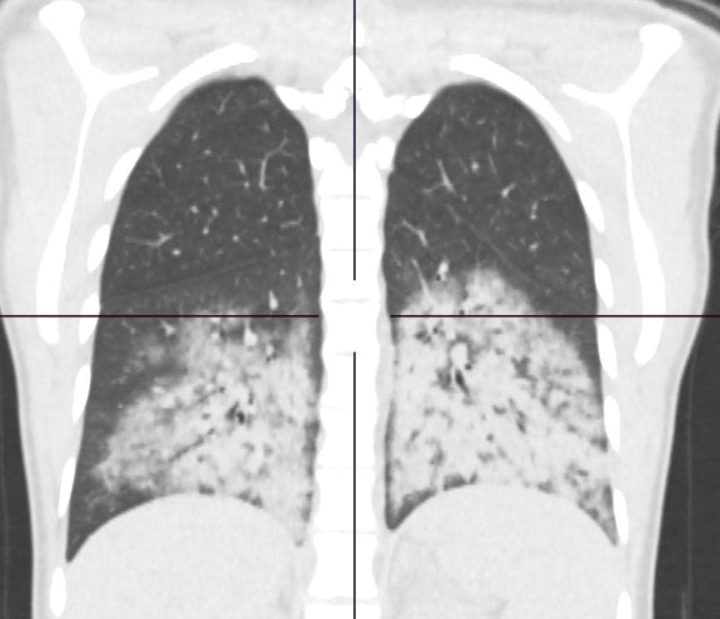

15 настай хүү уушгины хаван гэсэн оноштойгоор сэхээнд байсан аж.